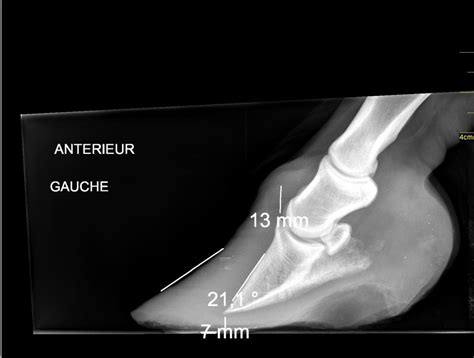

Bien que les signes cliniques soient souvent très évocateurs, la radiographie est un outil indispensable pour confirmer le diagnostic de fourbure et évaluer précisément sa sévérité. Les clichés radiographiques permettent de visualiser :

- Le degré de basculement de la troisième phalange vers l'avant.

- La distance entre la troisième phalange et la paroi du sabot (descente de la phalange).

- La mesure des angles et des épaisseurs de corne, fournissant des données quantitatives sur l'étendue des lésions.

La radiographie est également essentielle pour suivre l'évolution de la maladie au fil du temps et ajuster le traitement en conséquence. Dans certains cas, un phlébogramme, une radiographie avec injection d'un produit de contraste, peut être utilisé pour évaluer la vascularisation du pied et détecter d'éventuelles compressions vasculaires dues au déplacement de la phalange.